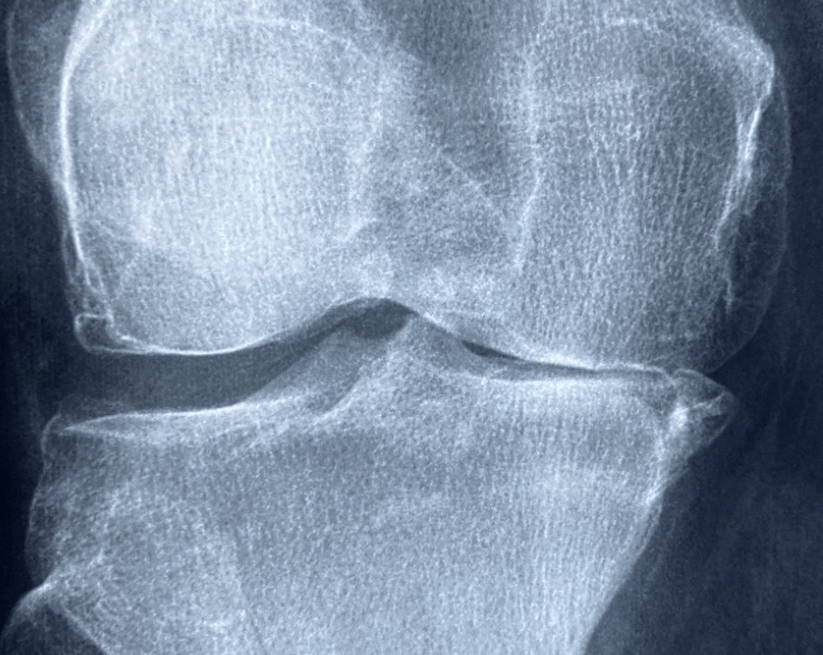

퇴행성관절염이란 무엇일까요?

퇴행성관절염은 관절을 보호하는 연골이 노화 또는 외상 등으로 점차 닳아 없어지면서

관절에 염증이 생기고 통증이 발생하는 질환입니다.

특히 무릎, 고관절, 손가락 등 체중이 많이 실리거나 반복적으로 사용하는 부위에서 자주 발생하죠.